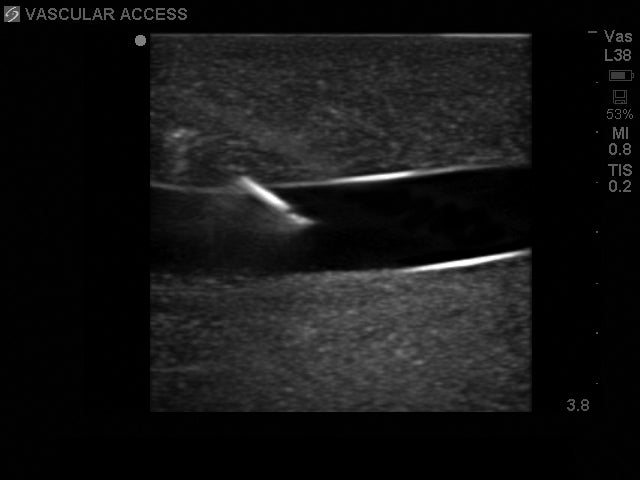

Realism, quality and durability. Blue Phantom's brand new Ultrasound Internal Jugular Central Line Training phantom offers you the realism that you expect, the quality that you demand and the durability that you deserve. Constructed utilizing Blue Phantom's ultra-durable and truly self-healing SimulexUS™ tissue, this compact central venous access internal jugular ultrasound phantom model provides you with superb ultrasound imaging characteristics and allows you to perform complete central line placements of the internal jugular vein – including needles, guidewires, dilation, and threading of catheters.

Our internal jugular central line ultrasound simulator offers superb internal and external anatomical realism. Developed using our innovative LifeCast™ modeling techniques, the external anatomy is present in tremendous detail and the internal anatomy matches that of human anatomy allowing you to practice and teach on this extremely lifelike central line manikin. Our specially designed tissues will never clog your needle and will always image like human tissue without unrealistic ultrasound system settings.

The light weight and portable internal jugular training manikin contains vascular anatomy including the internal jugular vein (IJ) and the carotid artery. Internal structures also include the trachea and clavicle providing you with superb realism – using any ultrasound system equipped with a vascular access ultrasound transducer. External landmarks also include a palpable suprasternal notch, trachea and clavicle. This central venous access ultrasound phantom is specifically designed for teaching and practicing internal jugular (IJ) cannulation; the training model accommodates both ultrasound guidance and blind insertion technique.

- Patented simulated tissue matches the acoustic properties of human tissue; optimize your training with superb ultrasound imaging characteristics

- Use with any ultrasound system and experience the same quality you expect from imaging patients in a clinical environment